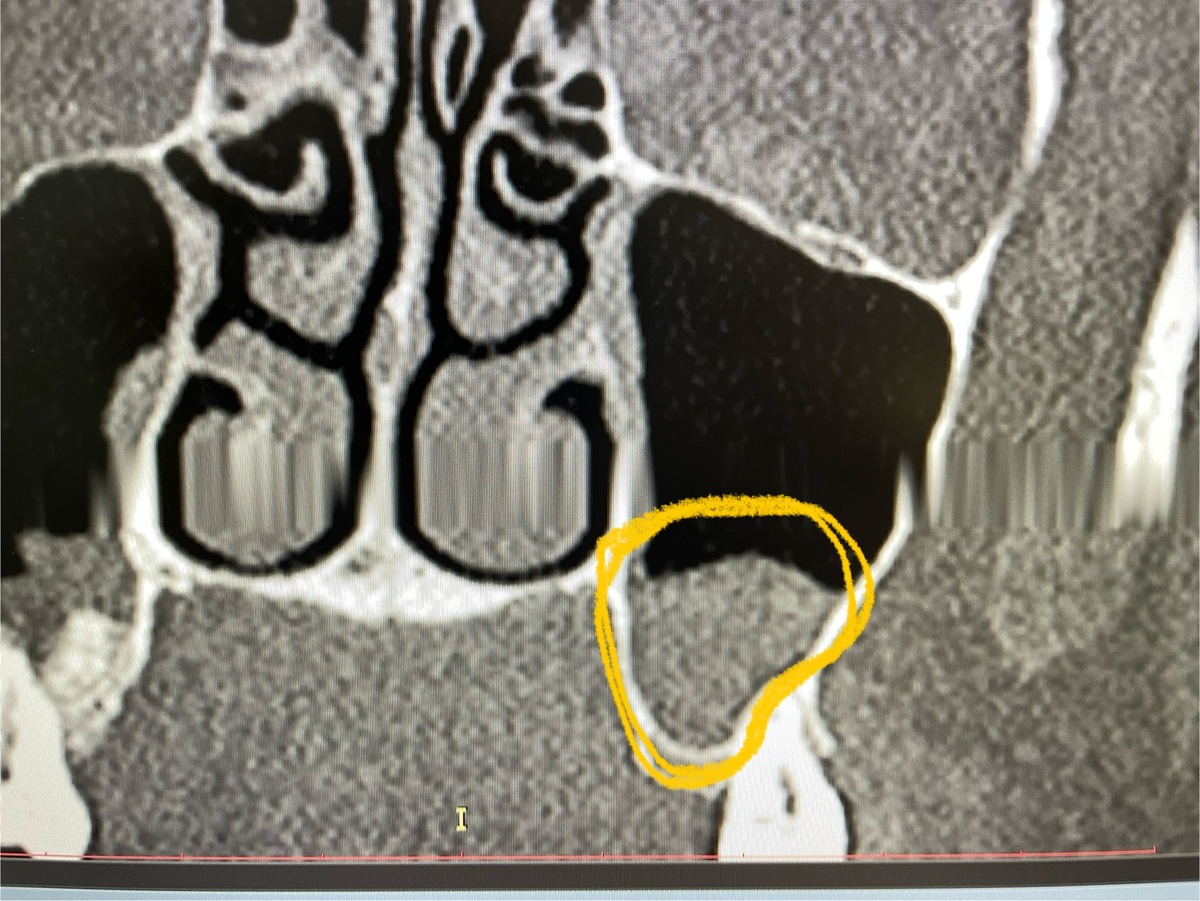

Дорогие читатели, спешу поделиться новым интересным клиническим случаем. Ко мне обратилась пациентка по поводу проведенной ей 2 месяца назад стоматологической операции под названием синус-лифтинг. Почему ко мне, ведь я ЛОР? Потому что это смежные области, и порой для осуществления следующих шагов (в данном случаем, установки импланта) нужно заглянуть немного дальше. Также на снимке пациентки обнаружилась ещё одна находка, о которой я сообщу в конце. Сначала небольшая справка, чтобы вы понимали, о чём речь: Синус-лифтинг представляет собой операцию по увеличению костной массы (и соответственно, толщины) верхней челюсти, с целью создания достаточной опоры для последующей установки зубных имплантатов. Операция может быть закрытой либо открытой. Проводится она следующим образом: в зоне имплантации делают отверстие, дно верхнечелюстной [гайморовой] пазухи смещают кверху, в полость вводят костнопластический материал и устанавливают защитную мембрану для фиксации материала и лучшего зажи

Синус-лифтинг. Выход материала в мягкие ткани. «Галя, у нас отмена!»